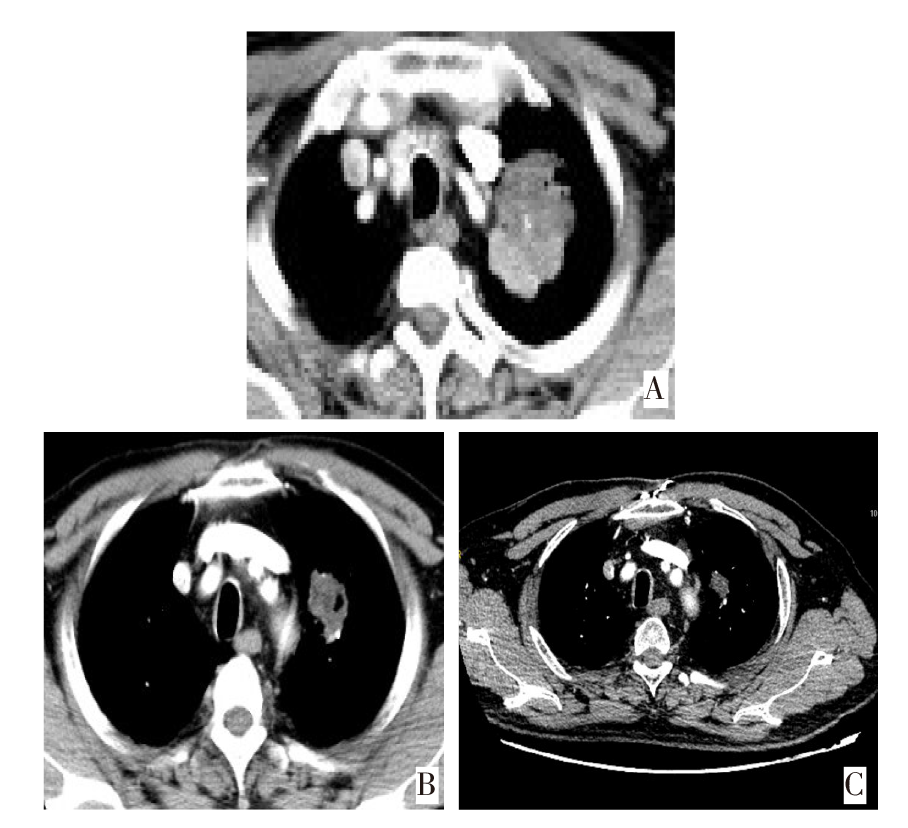

随着磁共振成像等影像学技术的不断发展,脑转移瘤的检出率越来越高。其中囊性脑转移发病率虽然远低于实性脑转移,但囊性脑转移瘤患者病情急,占位效应明显,是临床亟待解决的问题。既往文献报道囊性脑转移多见于乳腺癌和肺腺癌,特别是驱动基因阳性肺癌患者。该文报告1例以神经系统症状起病的小细胞肺癌囊性脑转移患者在多学科诊疗模式下获得临床治愈,在影像学动态评估以及微小残留病灶检测下避免过度治疗,延长生存期的基础上获得较高的生活质量。

With the continuous development of imaging techniques such as magnetic resonance imaging, the detection rate of brain metastases is increasing. Although the incidence rate of cystic brain metastasis is far lower than that of solid brain metastasis, patients with cystic brain metastasis are in urgent condition and have obvious space occupying effect, which is an urgent clinical problem. Previous literature has reported that cystic brain metastasis is more common in breast cancer and lung adenocarcinoma, especially in lung cancer patients with positive driver gene. This article reports a case of small cell lung cancer with cystic brain metastasis, which started with neurological symptoms, and was clinically cured under a multidisciplinary diagnosis and treatment model. Through dynamic imaging evaluation and molecular residual lesion detection, the patient can avoid overtreatment and achieved a relatively higher quality of life on the basis of prolonging survival.